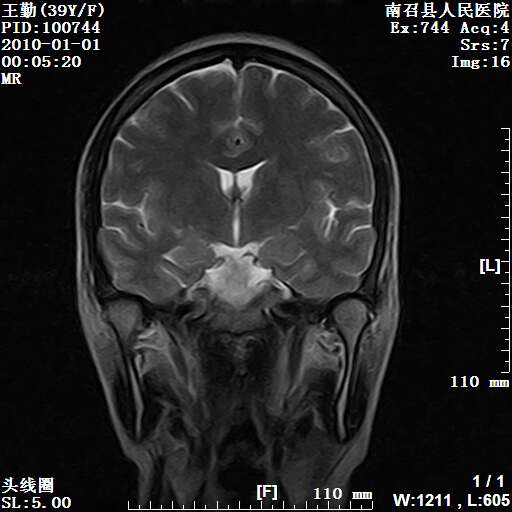

以下是引用随光逐影在2010-1-22 9:03:00的发言:[br]考虑左侧中颅窝(蝶骨翼区)脑膜瘤侵犯蝶骨翼并突入左侧眼眶。

以下是引用水过无痕在2010-1-22 14:55:00的发言:[br]一、定位:颅外占位;二、定性:恶性可能性大;三、组织来源:来源于左侧眼外直肌或其他部位;考虑为:横纹肌肉瘤>转移瘤>脑膜瘤.